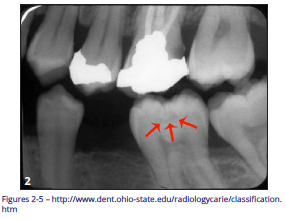

Pit and Fissure Caries (Figure 2)

Includes Class I occlusal surfaces of posterior teeth, lingual pits of maxillary incisors, buccal surfaces of mandibular molars.

Figure 2